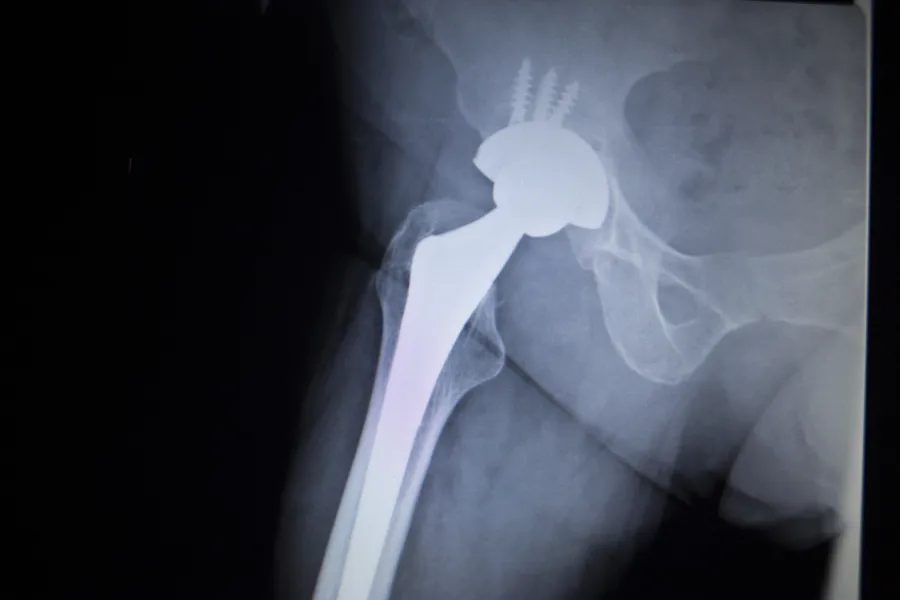

Alvorlige, dype infeksjoner i forbindelse med innsetting av hofte,- kne,- og skulderproteser er en fryktet komplikasjon. For pasientene medføre dette smerter og lange sykehusopphold. For sykehuset medfører det betydelig bruk av ressurser og penger. Å redusere disse komplikasjonene er derfor noe «alle» er tjent med.

Gule stafylokokker er en bakterie som er vanlig å ha både på huden og i munn/nese. Stort sett så forårsaker de ikke sykdom. Kommer de derimot under huden, så kan de fremkalle sykdom. Forbedringsprosjektet i Vestre Viken har derfor vært å finne en god metode for å hindre dype infeksjoner med gule stafylokokker i forbindelse med innsetting av leddproteser.

Behandlingsstrategien går ut på at man skal forsøke å sanere, eller fjerne, den naturlige forekomsten av gule stafylokokker i forbindelse med operasjonen. Metoden har vist seg særdeles effektiv.